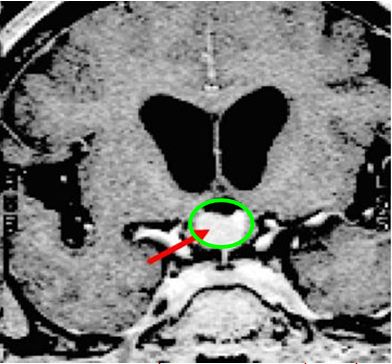

Sơ đồ khối u nhỏ vùng R nơi khối u xuất phát giữa dây thần kinh thị và ổ TB vảy, khối u có thể tồn tại và phát triển ở vị trí này, (R-site) là vị trí khó, có thể điều trị hiệu quả bằng hệ thống xạ phẫu dùng dao gamma quay